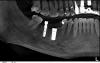

Archlich Опубликовано 4 июля, 2013 Поделиться Опубликовано 4 июля, 2013 Помогите, плиз, опознать имплантат.Установлен тонкий цилиндрический имплантат в области 47 зуба. Со слов пациента, ставил где-то в 2000 году в ЦНИИСЕ. Во вру у него стоит то ли формирователь, то ли ещё что-то (см. фото). Вертикальный винт с шестигранником, интерфейс - короткий конус и длинный внутренний шестигранник.Может кто узнает?? Ссылка на комментарий